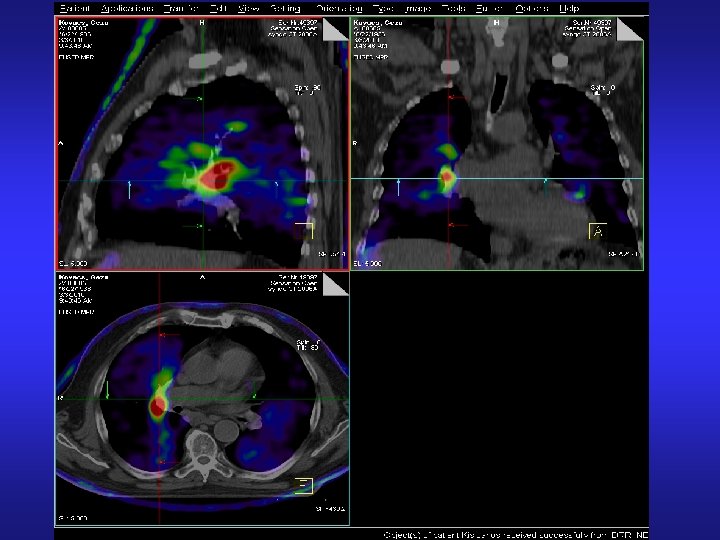

CT-PET fusion CT PET

More spectacular fusion of PET and CT • Easier to find the correct place of tumor, and involved tissue volume